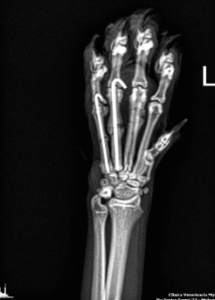

Gli interventi ortopedici sono procedure chirurgiche che trattano patologie dell’apparato muscolo-scheletrico, come fratture, lussazioni, displasie e problemi articolari. Si occupano di correggere deformità, riparare lesioni e migliorare la mobilità degli animali.

Fratture: Correzione e allineamento di fratture ossee.